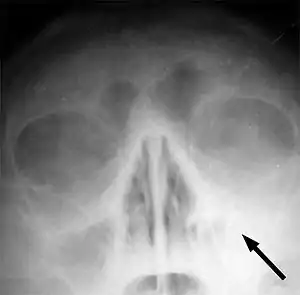

Синуси́т (лат. sinusitis), синонім синуї́т[3] — запалення слизової оболонки навколоносових повітряних пазух (sinus paranasales), частіше всього в лобній (фронтит) та верхньощелепній (гайморит) кістках.

Місце локалізації синуїтів відповідне до вказаних повітряних пазух.